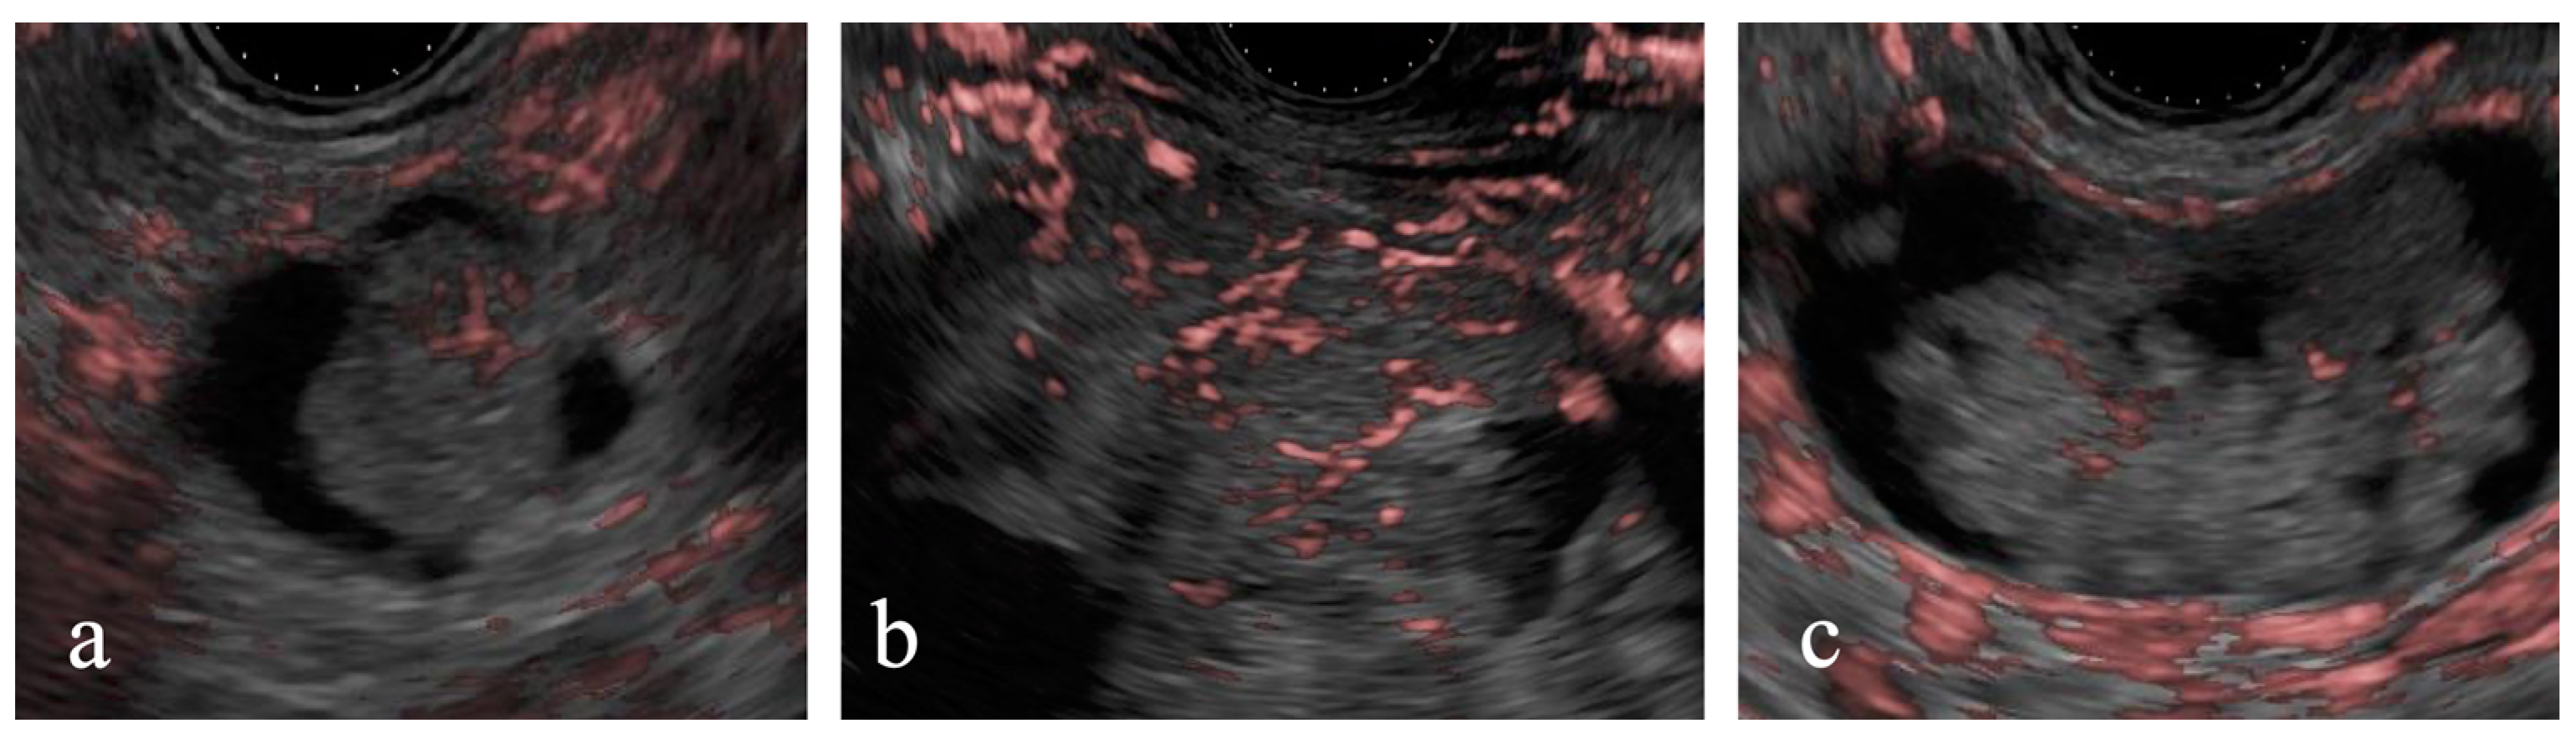

Of the 68 cases, 17 with enhancing MNs larger than 5 mm on CE-EUS were classified as having high-risk stigmata. Among these, DFI-EUS identified linear or dotted signals within the MNs in 14 (82%) cases. Surgery was performed for 13 of these 17 cases (Figure 5). The final pathological diagnosis of the surgically resected cases included low-grade dysplasia for six cases and intraductal papillary mucinous carcinoma for seven cases. Among the seven intraductal papillary mucinous carcinoma cases, DFI-EUS detected dotted signals in two cases and linear signals in four cases; one case was difficult to evaluate. Similarly, among the six low-grade dysplasia cases, dotted signals were observed in two cases and linear signals were observed in three cases; one case was difficult to evaluate. No significant association between the pathological diagnosis and DFI signal findings was observed (p = 1.00).

Figure 5. Detective flow imaging of mural nodules in surgically resected cases. Linear vessels are observed inside the mural nodule, intraductal papillary mucinous carcinoma (a,b), and low-grade dysplasia (c).